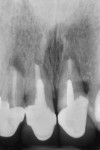

A 45-year-old female patient presented to a prosthodontist with a chief complaint that she had always disliked the slanted appearance of her upper front teeth (Figure 1). She had a congenitally missing maxillary left lateral incisor (tooth No. 10), and a very high smile line aggravated the esthetic situation. In addition, she was unhappy with the color of her porcelain crowns (Figure 2). She stated that she had multiple root canal treatments on her anterior teeth and endodontic surgery to try to save these teeth (Figure 3). The patient further stated that her general dentist had told her that the teeth could be crowned but that the prognosis was poor because of the failing root canals and periodontal bone loss and mobility. The general dentist had no plan to correct the slanted appearance of her teeth and referred the patient to the prosthodontist.

The endodontist felt that retreatment would be problematic because root canal therapy had been done multiple times and had included apical surgeries. Access to the canals on Nos. 8 and 9 would require removal of the crowns and posts. Additional apical surgery on Nos. 7 through 9 would most likely be needed.

The prosthodontist in the study group (not the original prosthodontist) suggested that teeth Nos. 8 and 9 were structurally and periodontally compromised even if endodontic retreatment could be successful. The periodontist was concerned about the 7 mm to 8 mm pocket depths and advanced mobility.2 It would be difficult to reduce the pockets and ameliorate the canted occlusal plane with osseous surgery.